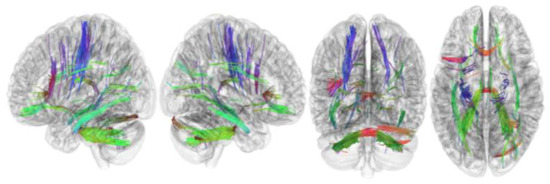

3.2. Tracks with FA Correlated with RLS Severity

| Tracks with positive correlation with RLS severity | Cerebellum, corpus callosum forceps minor, corpus callosum forceps major, corpus callosum body, and cingulum frontoparietal track |

| Tracks with negative correlation with RLS severity | Middle cerebellar peduncle, inferior longitudinal fasciculus, corticospinal tract, corpus callosum forceps minor, cerebellum, frontal aslant tract, dentato-rubrothalamic tract, inferior longitudinal fasciculus, corticostriatal tract superior, and cingulum parahippocampoparietal tract |